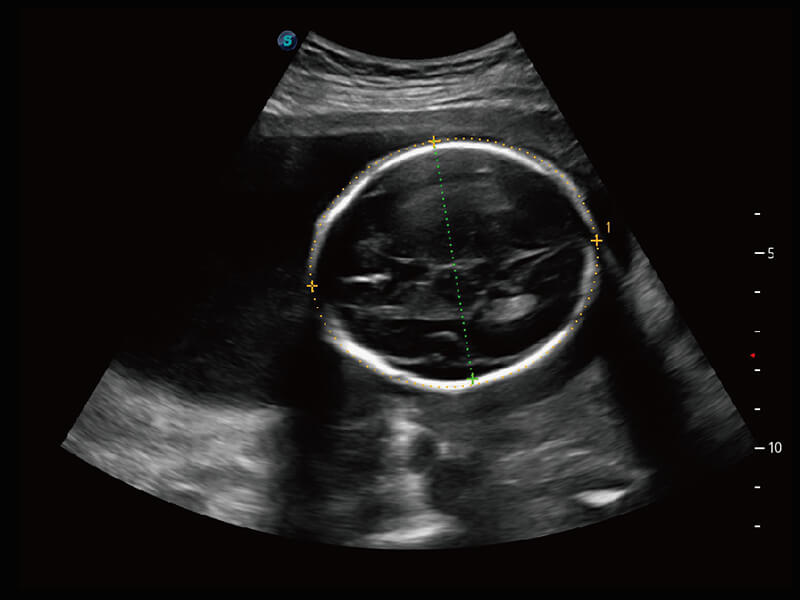

性能优异的硬件架构,极大提升超声系统的运行效率和数据处理能力。相比以往超声成像系统,Wis+平台为您带来极快的响应速度和成像帧频,提升检查流畅度。

S60探头工艺,从前端信号处理每一个环节采集无损声学数据,真实还原组织原貌,再现解剖细节。